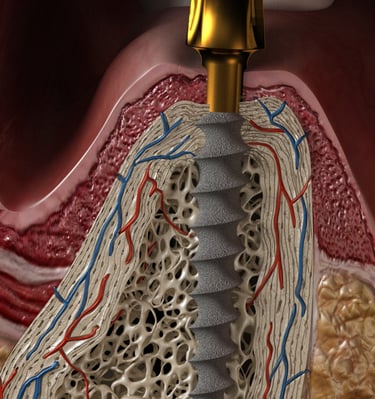

Implantes Monobloque

Implantes dentales sin cirugía.

Sin abrir encía.

Sin puntos de sutura.

Ideal para personas con poco hueso o edad avanzada.

Dientes inmediatos / 24 horas .

Implantes dentales innovadores

Implantes

Implantes monobloque sin cirugía y dientes inmediatos.